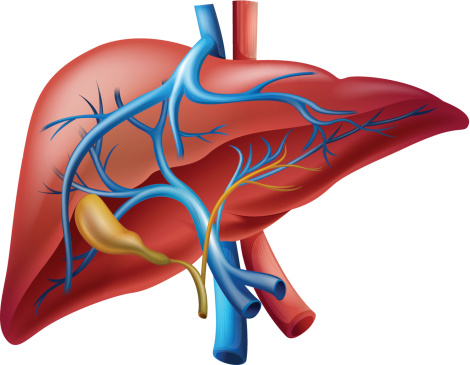

Alcoholism is an ever growing problem faced by societies throughout the world. About 86 percent of Americans over the age of 18 reported drinking at some point in their lifetime. Alcohol Awareness Month, held on April of every year, aims at increasing awareness about its causes, treatment, and recovery. This year the theme is “Changing ...click here to read more